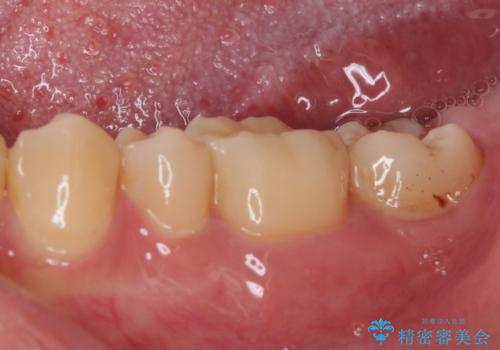

- 今まで色々と修復を重ね、いよいよものが挟まるとのことで来院された患者様です。

ものが挟まるだけであれば、インレーによる修復治療を選択しますが、今までの治療後が黒く汚く見えるとのことで、オールセラミッククラウンにて補綴治療を行うこととしました。